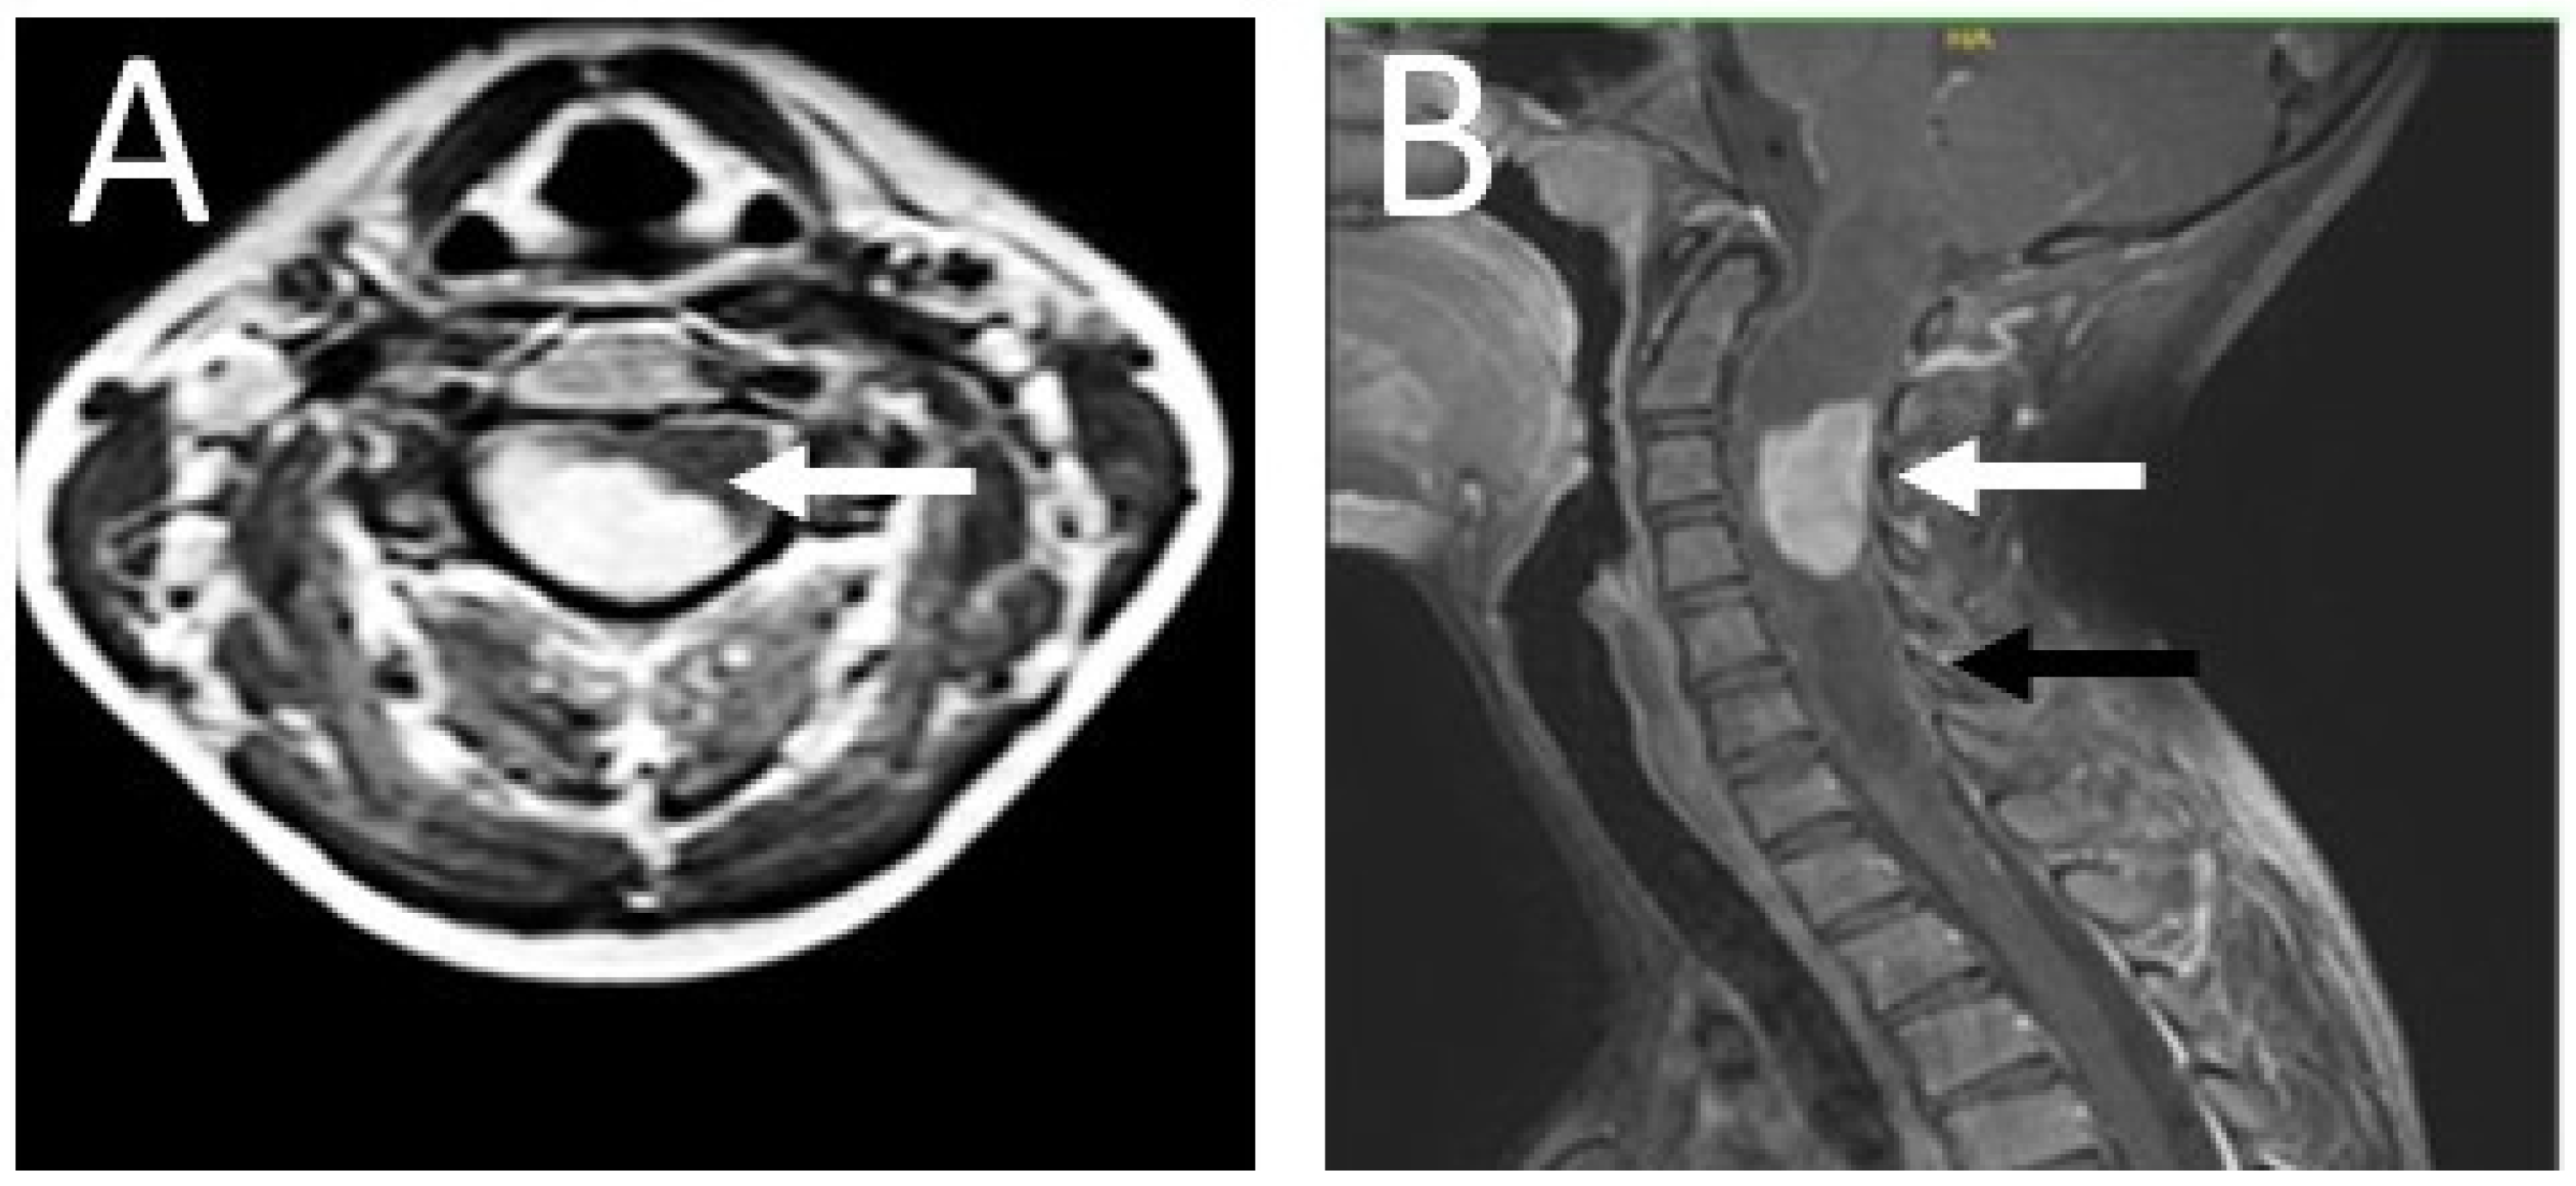

On 27 April 2018, a 13-year-old girl was admitted to the Department of Neurosurgery at the Polish Mother’s Memorial Hospital, Research Institute. The patient complained of progressive weakness of the right upper limb, accompanied by numbness of the first, second, and third fingers of the right hand. Sensory disturbances began in November 2017. On admission, neurological examination revealed weakness of the muscles of the right hand (Lovett 3) and right forearm (Lovett 4). She showed lack of postural control and a right-sided Romberg’s sign. The right upper limb paresis with weak tendon reflexes was caused by a lower motor neuron lesion. Magnetic resonance imaging (MRI) revealed a right-sided C3–C4 intramedullary tumor. It was accompanied by a syringomyelic cavity C1–C7 (Figure 1). The fluid reserve surrounding the cervical spine at the level of the lesion was completely depleted.

Figure 1.

Contrast-enhanced T1 MRI of the patient’s cervical spine. (A) The axial section at the C2 level; (B) the sagittal section. The photos were taken before the procedure. An intramedullary tumor is located in the spinal canal between the C2–C4 levels (white arrow), accompanied by a syringomyelic cavity extending throughout the spinal cord from the hindbrain to the cervical spine at the C7 level (black arrow). Due to the dynamic neurological symptoms, characteristic of the expansive process in the spinal cord, and the need for urgent surgery, imaging diagnostics were limited to the spinal cord and the cervicocranial border. An MRI of the brain was performed at a later stage.